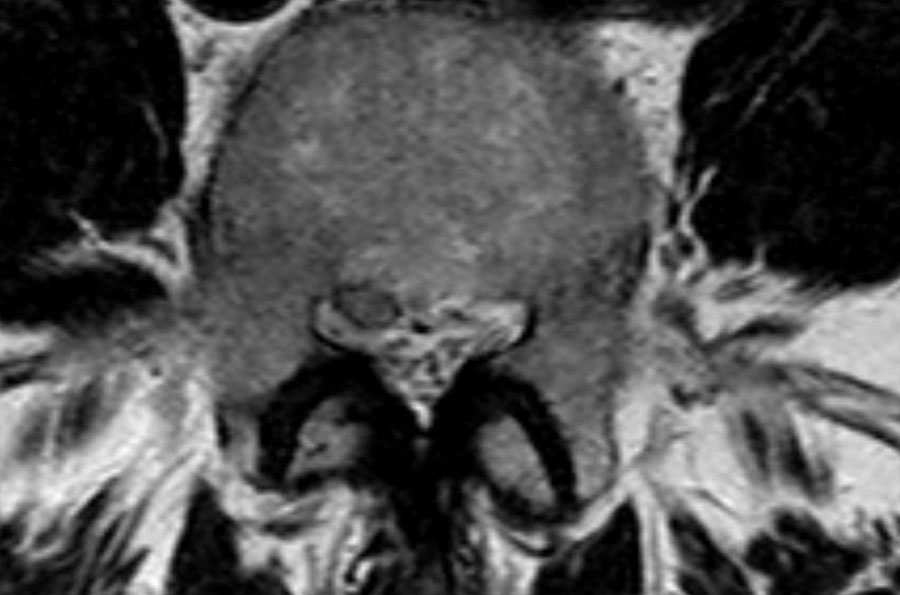

Cuộn qua các hình ảnh để quan sát đường đi của các rễ thần kinh tại mức độ đĩa đệm, ngách bên, lỗ liên hợp và ngoài lỗ liên hợp.

Tại mỗi mức độ có thể thấy các bệnh lý đặc trưng, nhưng có sự chồng lấp đáng kể.

Ngoài ra còn có rách vòng sợi (tăng tín hiệu) là nơi đĩa đệm thoát vị qua (mũi tên vàng). - Tại mức ngách bên, có thoát vị khu trú của chất đĩa đệm gây chèn ép rễ thần kinh L5 (mũi tên vàng).

Đây được gọi là thoát vị thực sự (extrusion), vì khoảng cách giữa các bờ của khối thoát vị lớn hơn khoảng cách tại nền. - Rễ thần kinh L5 bị chèn ép (mũi tên xanh dương) trong ngách bên.